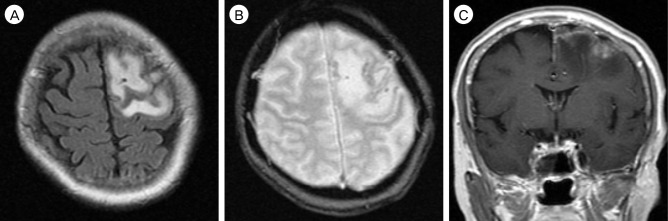

我们报告了一例硬脑膜动静脉瘘(DAVF)病例,在四个月的随访期间,患者的静脉引流模式自发地从 Borden II 型转变为 III 型。入院时,患者的神经系统状况恶化,并出现新的癫痫发作。入院后,使用 Onyx® 通过脑膜中动脉进行了血管内栓塞治疗。血管造影证实硬脑膜动静脉分流完全阻塞,患者的临床症状有所改善。虽然大多数硬脑膜动静脉瘘病例的临床过程和转归模式都是良性的,但仍需密切随访,以发现潜在的恶化。

We report a case of dural arteriovenous fistula (DAVF) that showed spontaneous conversion of venous drainage pattern from Borden type II to type III within a four month period of follow-up. Upon admission, the patient presented with aggravated neurologic status and newly developed seizure. After admission, endovascular embolization was performed through the middle meningeal artery with Onyx®. Complete obliteration of dural arteriovenous shunt was confirmed by angiography, and the patient's clinical symptoms improved. Although most cases of DAVF show benign clinical course and conversion pattern, close follow-up is required to detect potential aggravation.